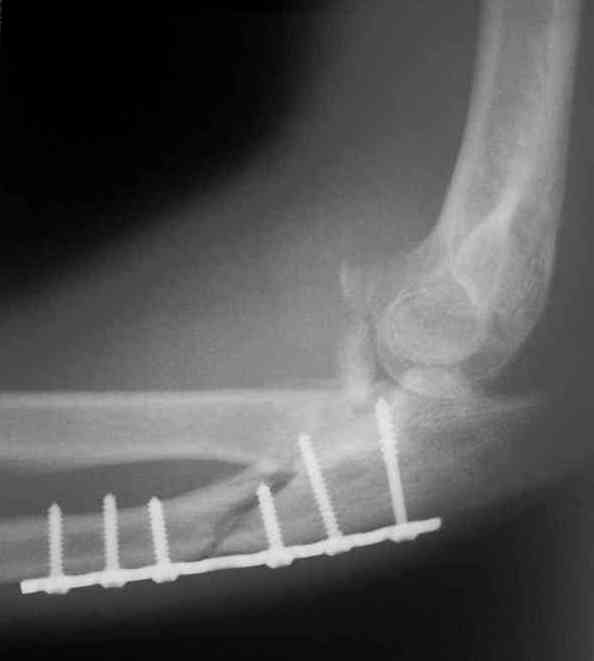

Re: Несросшийся перелом локтевой кости, подвывих предплечья кзади.Перелом венечного отростка. Состояние после резекции головки лучевой. Травма 4 мес. назад.

Был выполнен МОС локтевой пластиной,

Иммобилизация после операции 3 нед.Через 3 мес. на Rg несращение локтевой, подвывих предплечья кзади, осификаты в обл. венечного отростка.

Планируем оперировать - синтез локтевой с костной пластикой, попытаемся воcстановить связки.

Больной наблюдался в поликлинике,к нам попал

через 3 мес. Отмечается контрактура локтевого сустава, сгибание/разгибание 30/0/0.

МРТ у нас нет, сделаны томограммы.

МОС означает металлоостеосинтез.